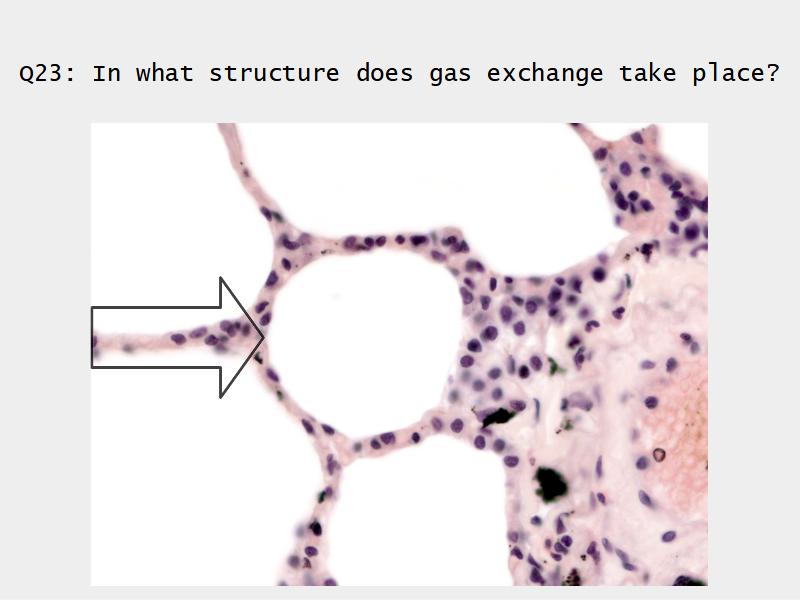

- Alveoli

Lungs